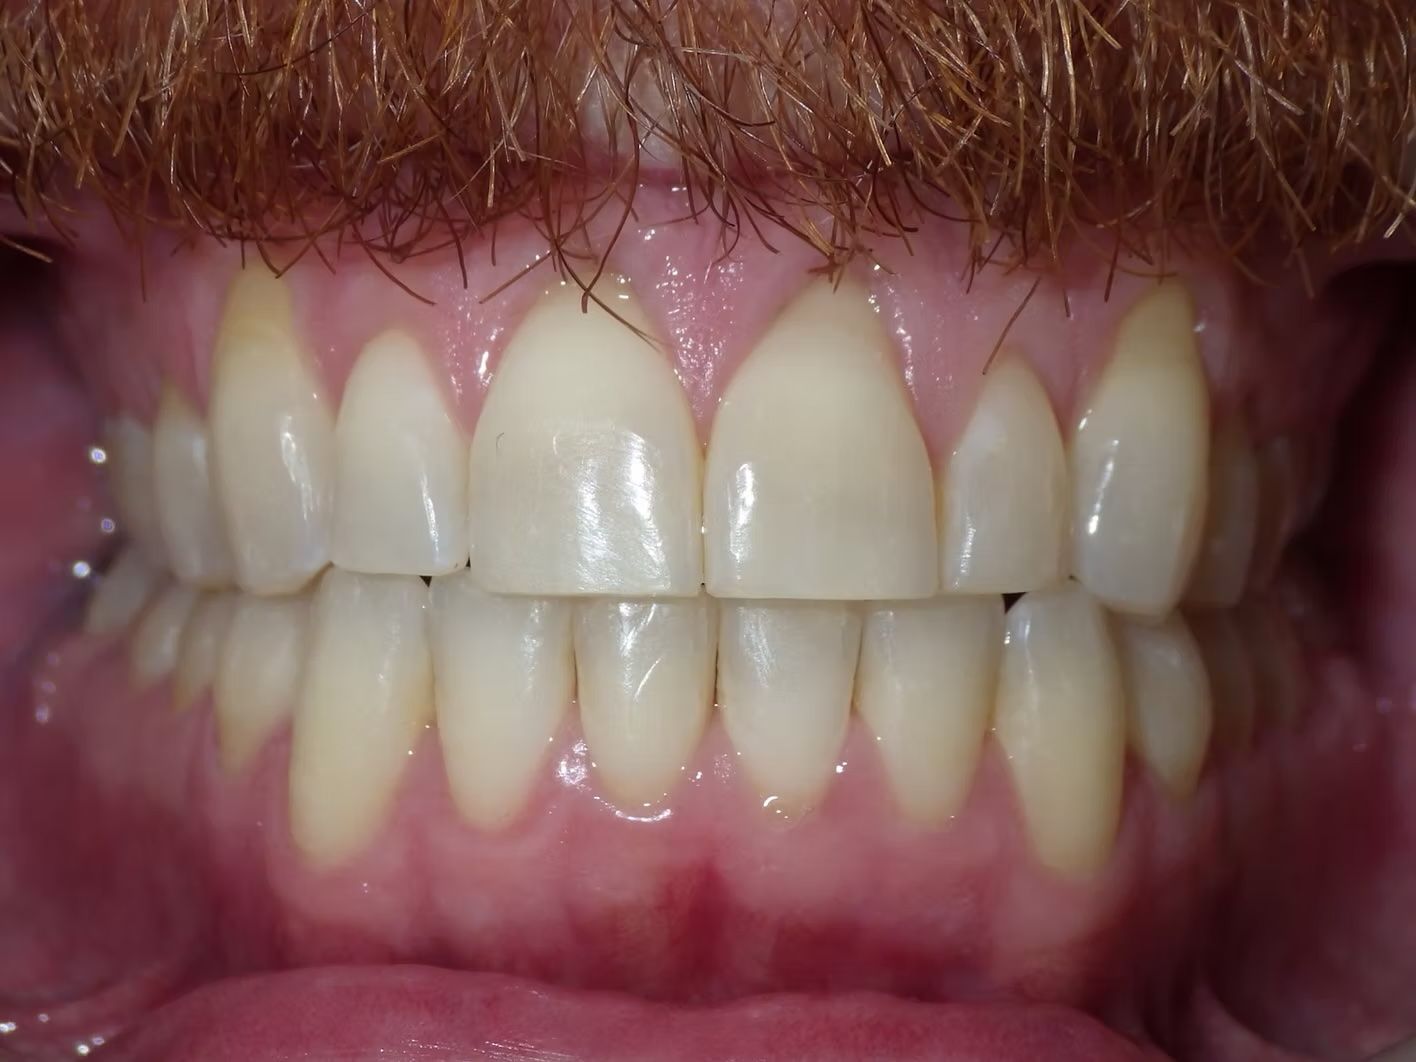

IAN

Ian came to the office because his lower teeth were crowded and he had an anterior cross bite. With traditional braces we resolved the crowding and aligned the teeth without causing flaring of the incisors and giving him a handsome smile. The treatment lasted 18 months and the final photos are at a 2 year follow up when we made him a new clear retainer.